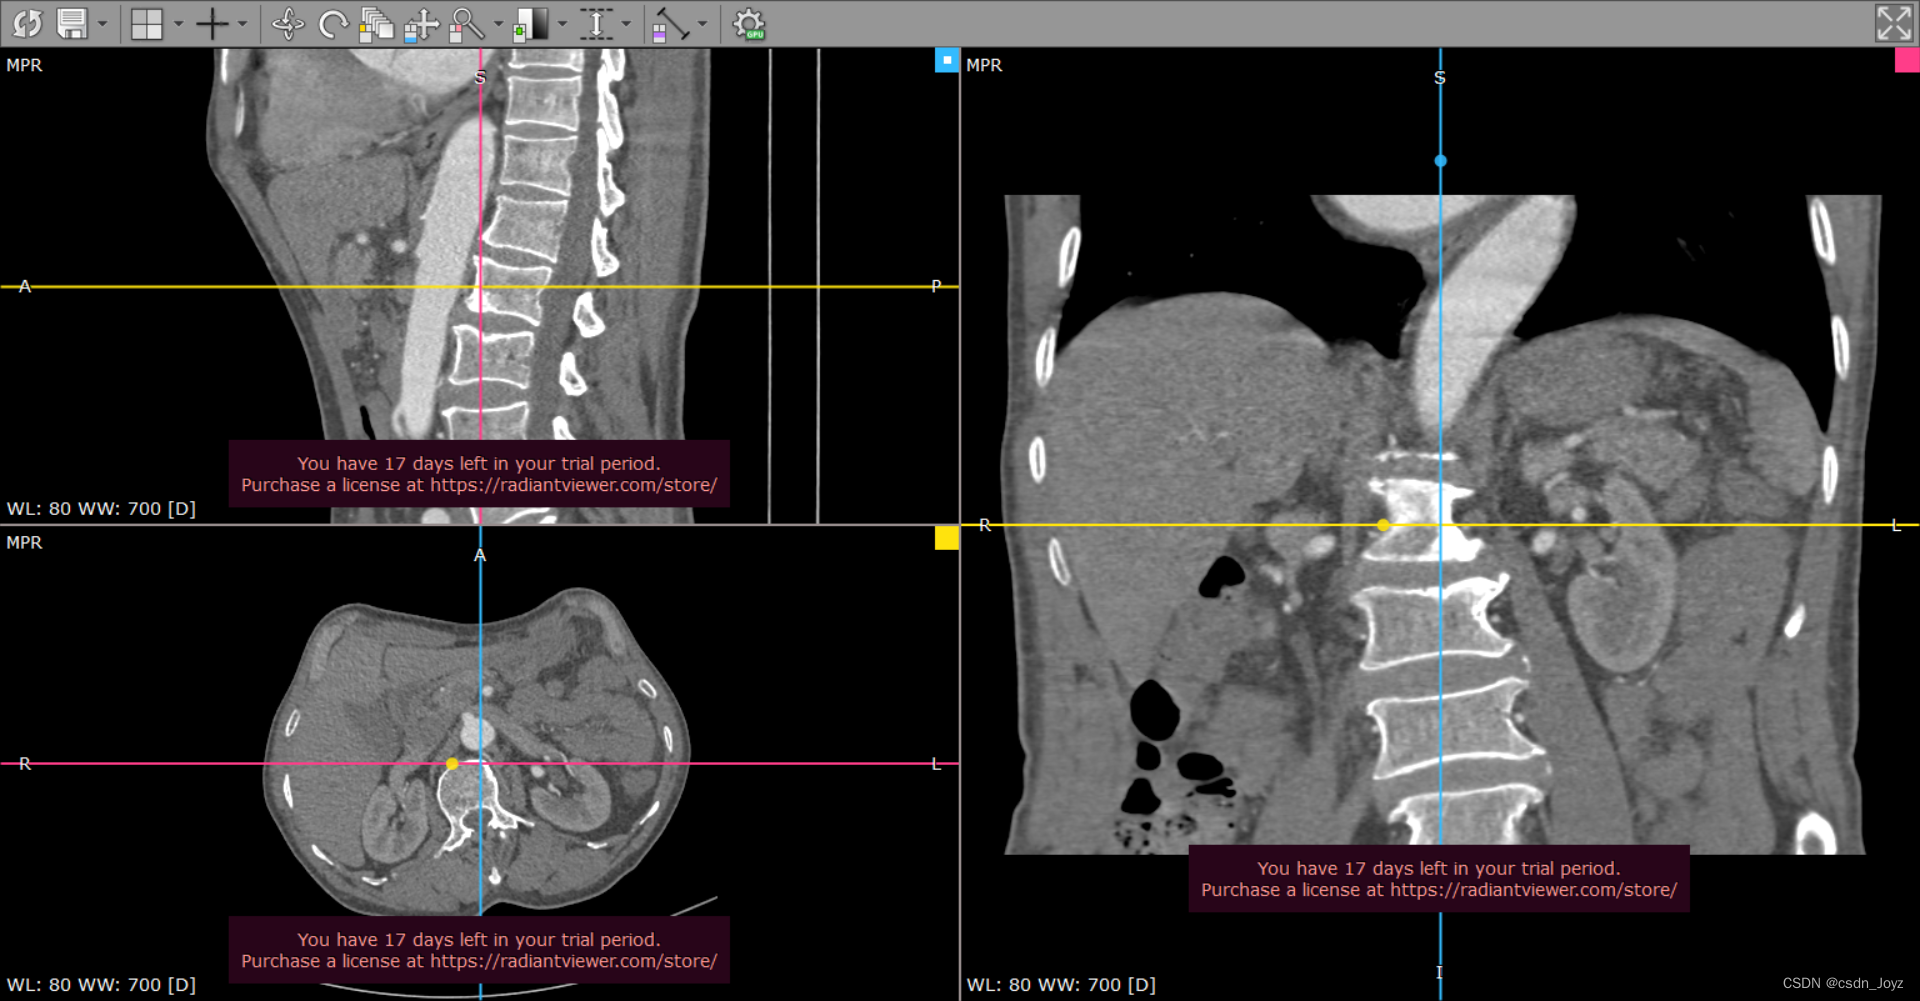

如图所示,多平面三维重建即根据影像数据重建出影像横断面、矢状位、冠状位图像,且切面可以进行角度、位置调整。